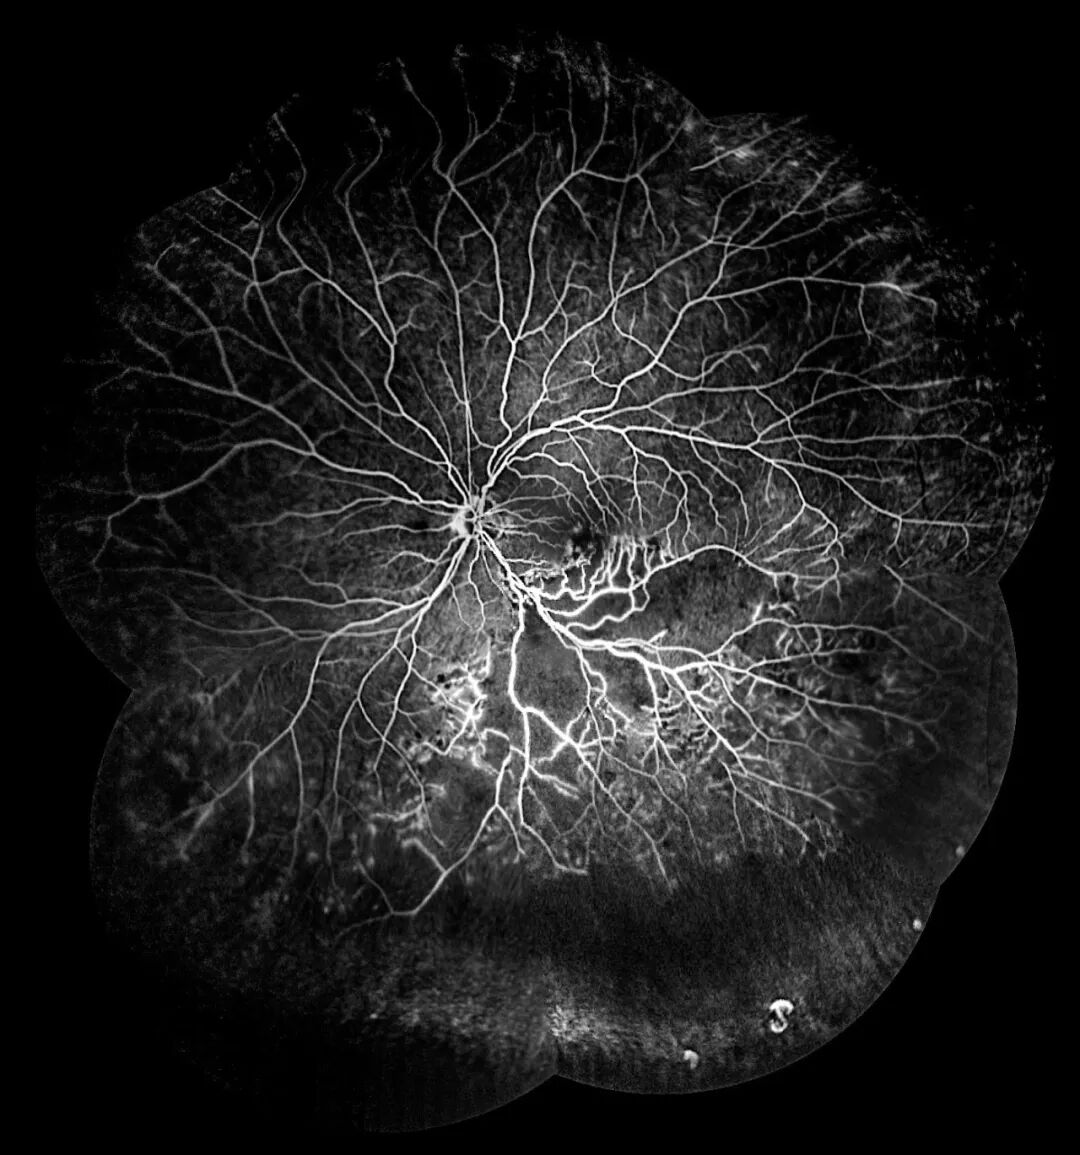

视网膜分支静脉阻塞